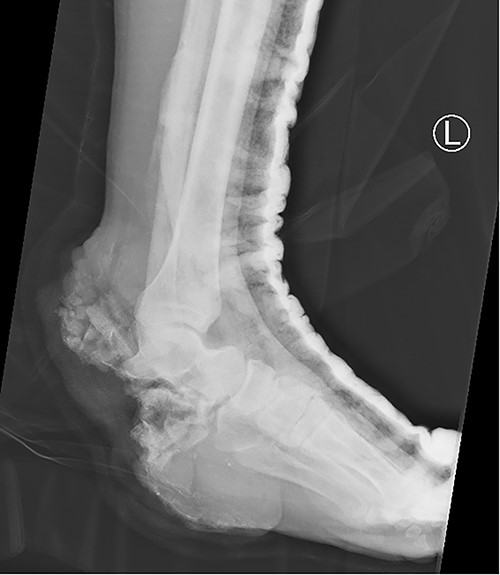

The treatment of calcaneus fractures is a challenge because of inadequate vascularity of this region [5]. Open fractures of the calcaneus are rare, ranging between 0.8 and 10% of all calcaneal fractures, and there are only a few reports described so far [6–9]. Further complicating their management, open fractures of the calcaneus carry higher incidence rates of infection, which range from 37 to 60% [7–9]. Treatments of complex calcaneal fracture include muscle and myocutaneous flaps, partial calcanectomy, total calcanectomy and below-the-knee amputation [8]. Traditionally, amputation has been the treatment of choice for extensive involvement of the calcaneus [5,10]. Recently, muscle flaps with skin grafts have become the preferred choice when filling wounds that have osteomyelitis at the base [8]. The aim is to facilitate the initial phase (heel strike) of the gait cycle, and rearrange the distribution of pressure over foot [9]. Due to the rare occurrence of open calcaneal fractures, there is a paucity of published data on soft tissue reconstruction alone for these injuries in the orthopedic and reconstructive surgical community. Our patient had a large calcaneal bone and soft tissue defect; thus, we selected a tensor fascia lata free flap alone for reconstruction of the defect. Advantages of this flap include reliable blood supply, bulky subcutaneous tissue and fascia, which can be used to cover large defects [9]. For this flap, the vascular pedicle anatomy is more constant [11]. Other advantage of this flap is its hidden and less visible site; minimizing aesthetic concerns [8]. In our patient, weight bearing was initiated 1 month after surgery. At 18-month postoperatively, the patient had a near normal painless gait, normal plantar sensation and no difficulty climbing or descending stairs with stable talonavicular joint (Fig. 4). The patient recovered near full range of motion and complete independent mobility.

X-ray of the left foot 18 months post flap coverage showing a stable talonavicular joint.